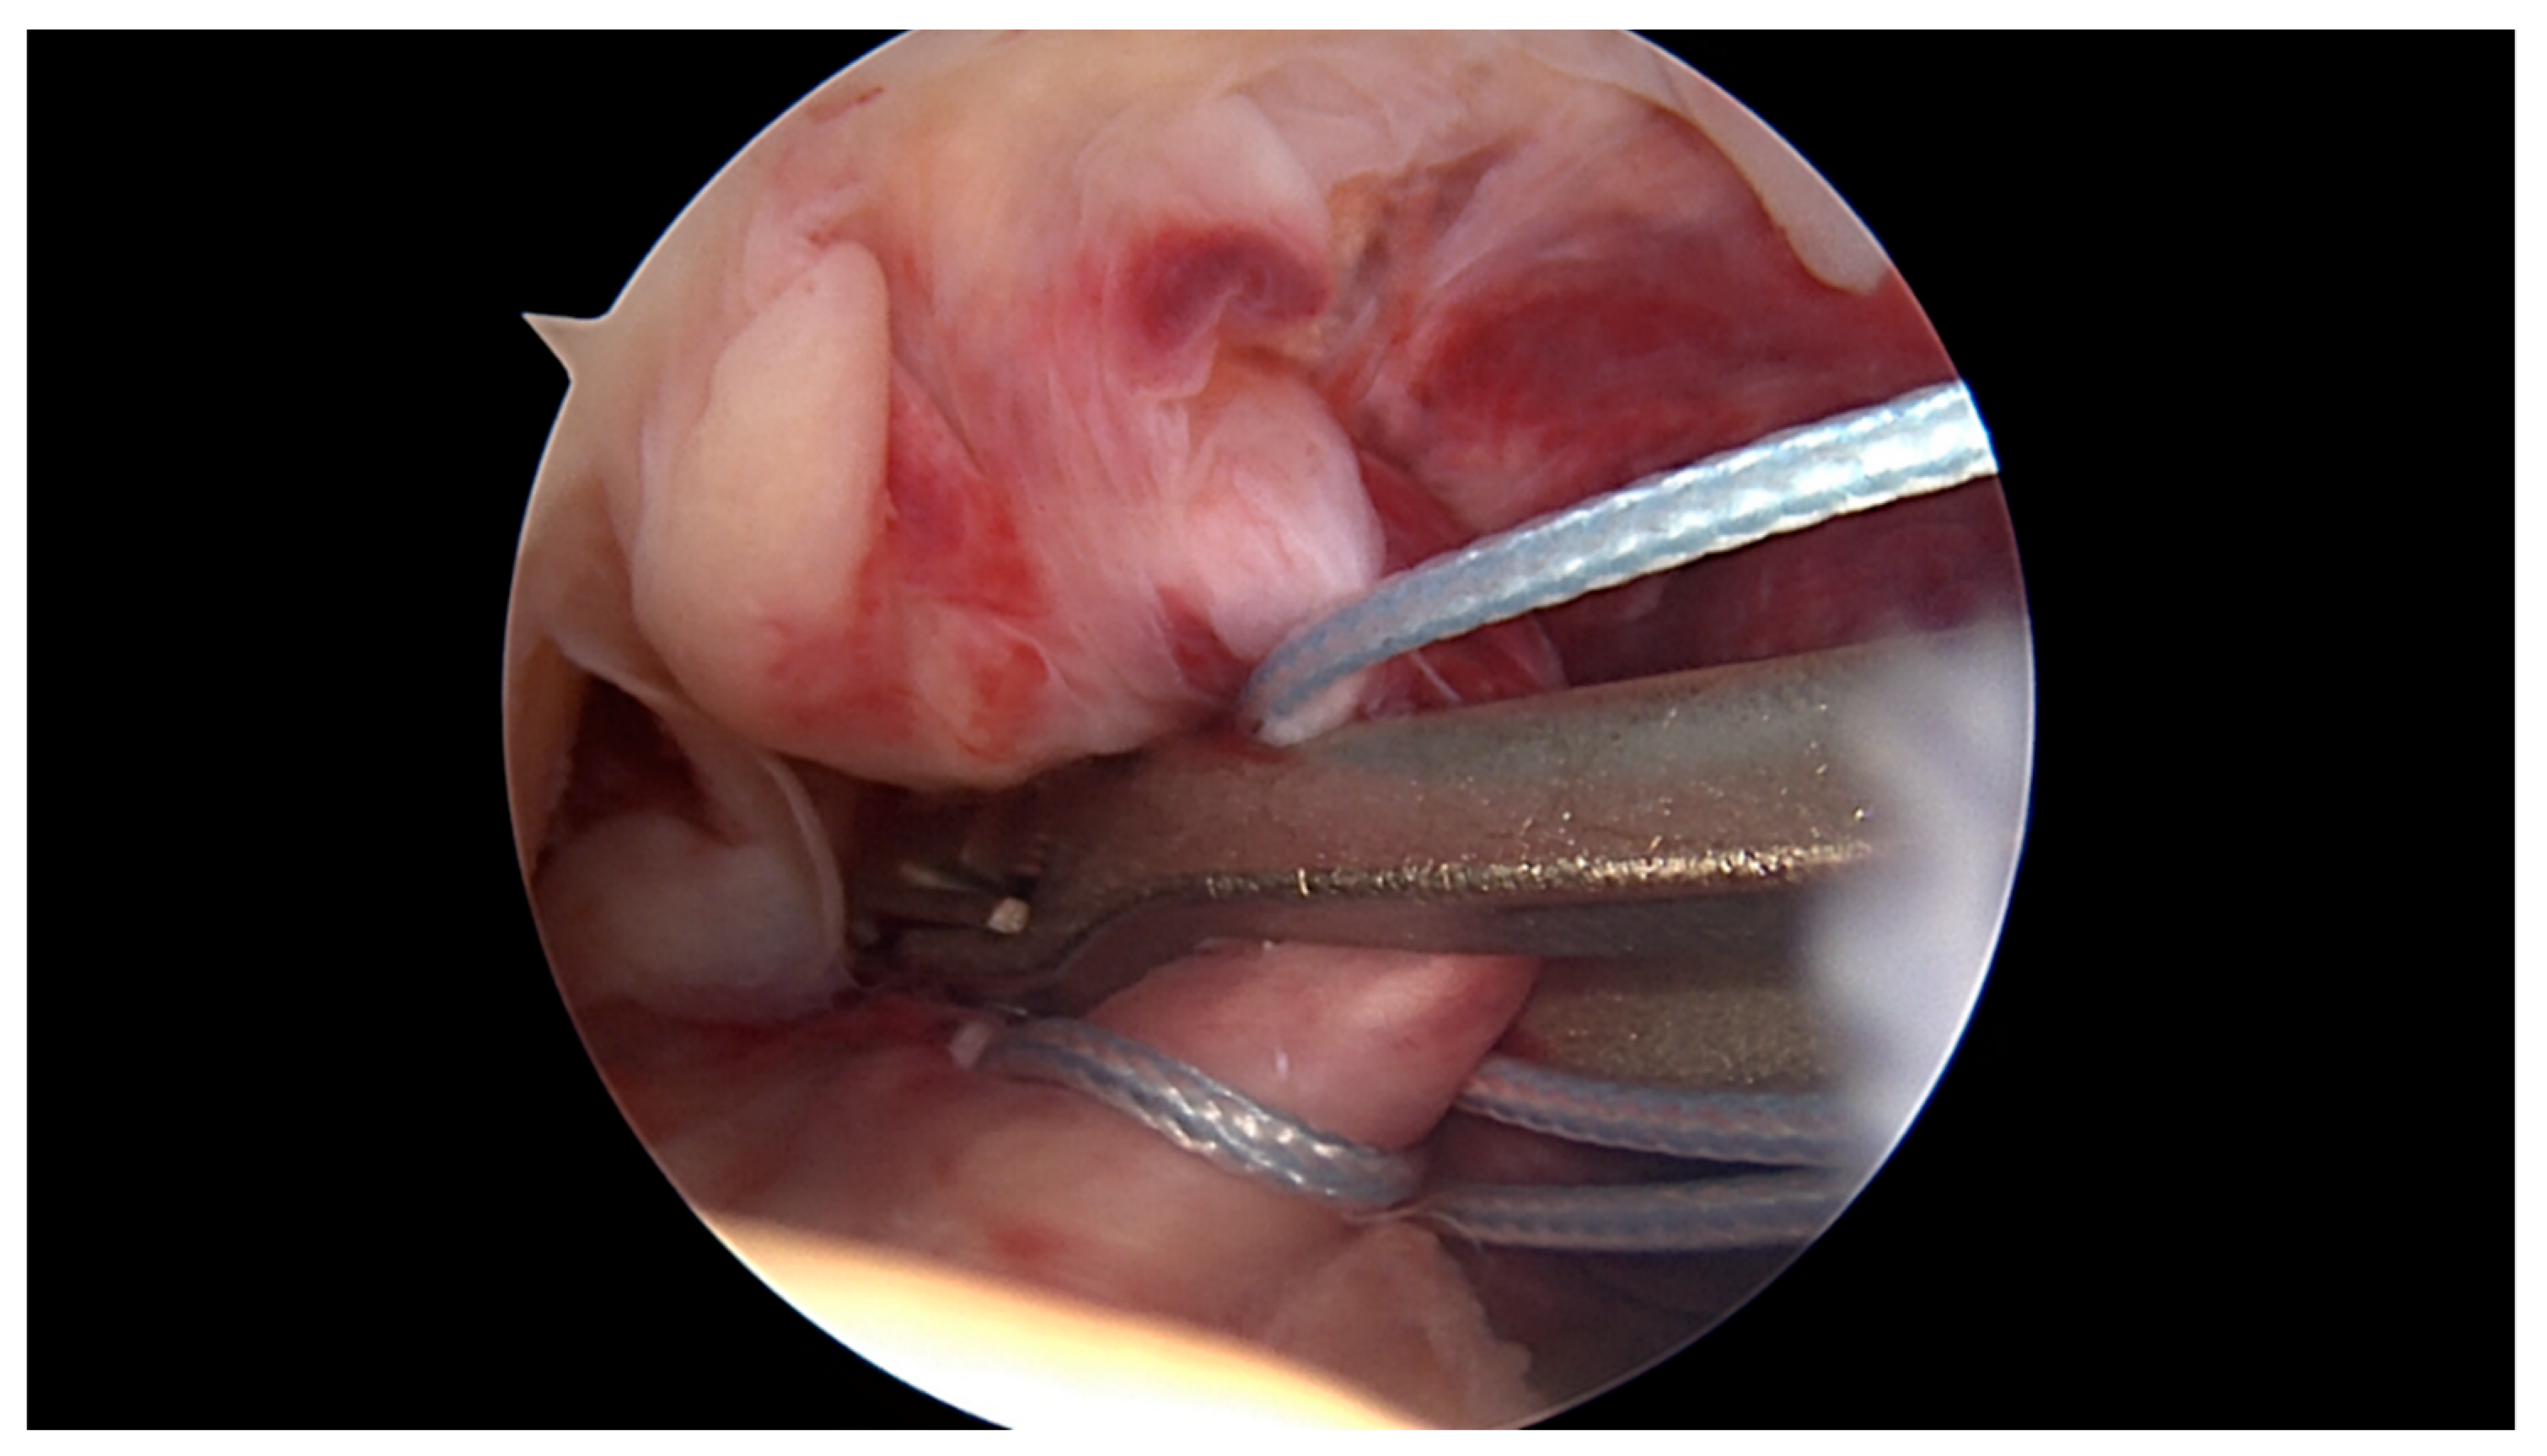

2.1. Surgical Technique and Rehabilitation